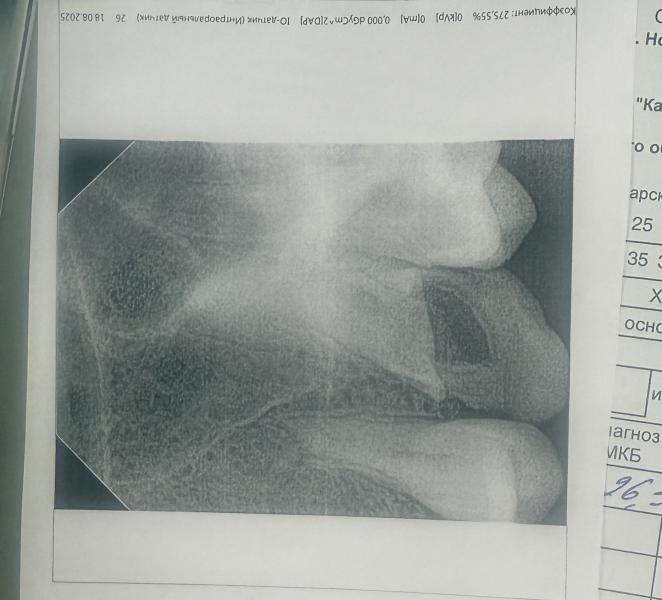

Можно ли спасти зуб с гноем на десне при ГВ?

post image

Можно ли спасти зуб? Поставить коронку и тд?

У меня на десне гной выходит. Но зуб никак не болит и не тревожит.

Она говорит там инфекция и тем более гв, лучше удалить.